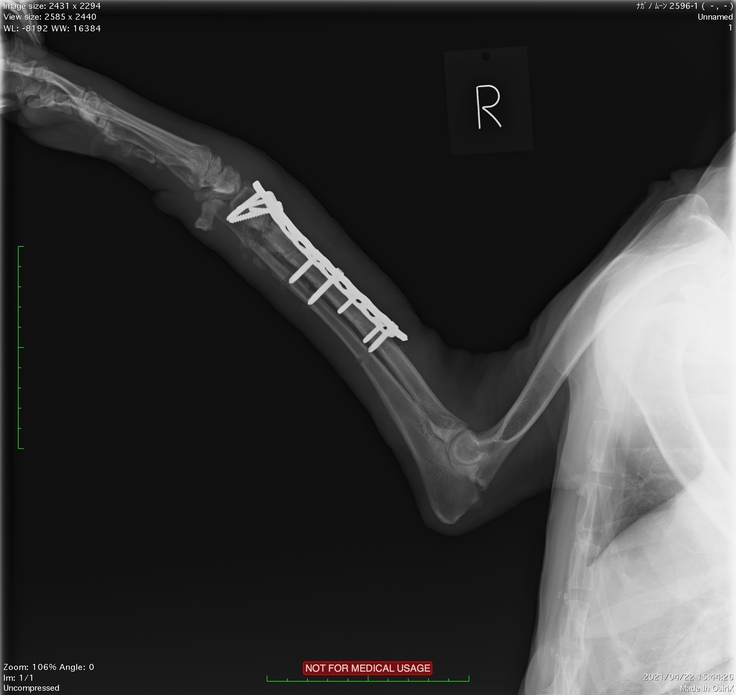

大津動物クリニックではクラウドファンディングのお話をしたらレントゲンの画像もご提供いただけました。

2度目の手術後のレントゲンです。まっすぐになりました。

右前足の開放骨折 2度のプレート固定手術